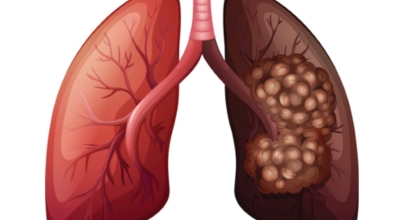

폐에 발생된 악성 종양을 말하며 오랜 기간 흡연해온 남성들에서 발병률이 높고 요즘 들어 가지가지 환경적인 요인의 영향과 간접흡연으로 흡연하지 않는 여성에서도 많이 발생하고 있답니다. 증상을 느껴 병원을 찾았을 때는 수술하기 늦은 경우가 많아 사망 확률이 매우 높은 암입니다. 폐 자체에서 생기거나 다른 장기에서 발생된 암이 폐로 전이되어 나타나기도 하고 특별한 초기 증상이 없는 경우가 많으며 암이 진행된 후에도 일반적인 감기 증상인 기침과 가래 외의 특이 증상이 나타나지않아 증상만으로는 진단이 쉽지 않아요.

폐암은 3기 이상인 말기에 발견되는 경우가 일반적으로라 예전에는 폐암 판정을 받으면 곧 사망이라고 부르는 말까지 있어요. 하지만 현재는 의료기술이 발달하여 폐암 5년 생존율은 70%가 넘고 있어요. 무엇보다 주기적인 건강검진으로 인해서 폐암을 조기에 발견한 경우가 많아서라고 볼 수 있답니다. 세세히 살펴보면 인산화효소 변이 폐암 환자의 경우 5년, 상피세포 성장인자 수용체 변이 폐암 환자의 경우 1년~3년의 생존율을 보인다고 해요. 하지만 요즘도 폐암을 3~4기에서 확진 받는 경우가 많아요.

폐암 검사는 X-ray를 통해서 검사하는데 , 크기가 작거나 구석에 위치한 경우 확인이 어려운 경우도 있습니다. 그리고 조직 검사를 통해서 정확한 진단을 하게 돼요. 폐암이 발견되면 종양의 크기나 전이 여부 , 위치에 따라서 수술 여부를 결정하게 돼요.

수술 치료

악성 종양이 있는 폐의 일부를 절제하는 방법입니다. 초기에는 내시경 기구를 활용하여 수술이 가능하기도 해요.

항암 치료

항암제를 이용한 치료 방법입니다. 폐암 4기 같은 경우에는 항암 화학요법이 유일한 치료방법이기도 해요. 폐암에 대하여 알아봤는데요.